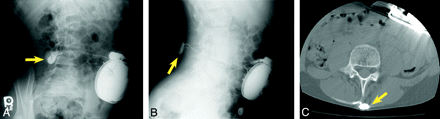

AP (A) and lateral (B) radiographs demonstrating a discontinuous segment of the catheter, with broken catheter ends in the subcutaneous tissue of the lower back (white arrow) and the spinal canal (yellow arrow).

The combination of a standard abdominal radiograph, AP and lateral lumbar spine radiographs, and an AP thoracic spine radiograph usually fully visualizes the entire pump and catheter system,34 though proper imaging technique is crucial with respect to these plain radiographs to assess the entire subcutaneous course of the tunneled catheter. Plain films can be inconclusive, however, because simple anatomic visualization of the catheter and pump fails to provide information about catheter patency, occlusion,38 or leaks.

AP (A) and lateral (B) radiographs as well as an axial CT (C) image show extravasated contrast material (yellow arrows) surrounding the catheter connector in the subcutaneous tissues of the mid-lower back, where it turns anteriorly toward the spinal canal.